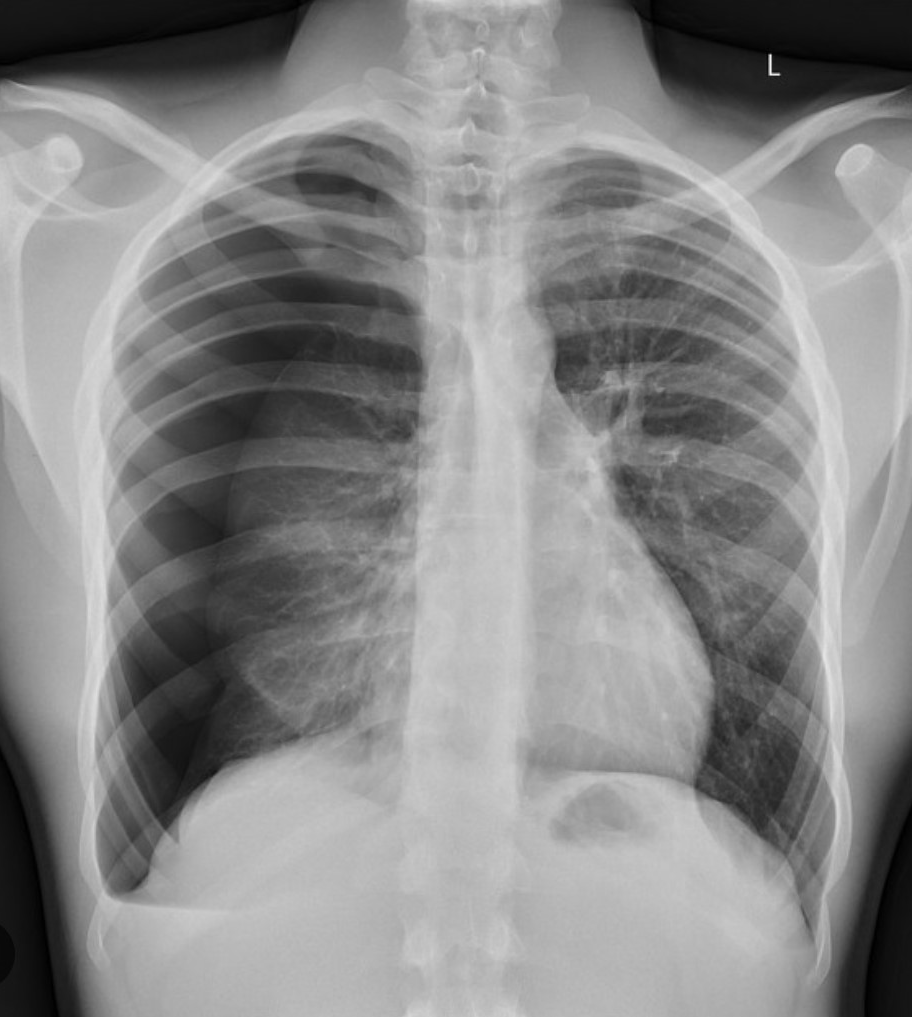

RRT for respiratory distress and this CXR.

What steps do you take next?

BiPAP

Lasix

(Can use nitro drip if patient in hypertensive emergency)